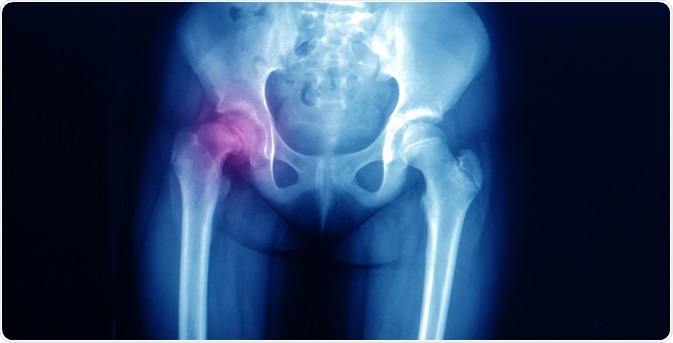

SCFEImage Credit: Yok_onepiece / Shutterstock.com

Biplanar X-rays are the primary study tool for this condition as they provide an accurate picture of the state of the bone. Supine anteroposterior and frog-leg lateral (Lauenstein) views are often requested to identify the pathology.

The pre-slip condition is signaled by a slight widening of the growth plate.

Early signs of slippage include joint capsule swelling, the presence of widening of the physis, and decalcification of the edge of the femoral shaft adjacent to the epiphysis.

A mild slippage is present when the femoral neck extends right up to the edge of the epiphysis.

The femoral head is displaced posteriorly with respect to the femoral neck.